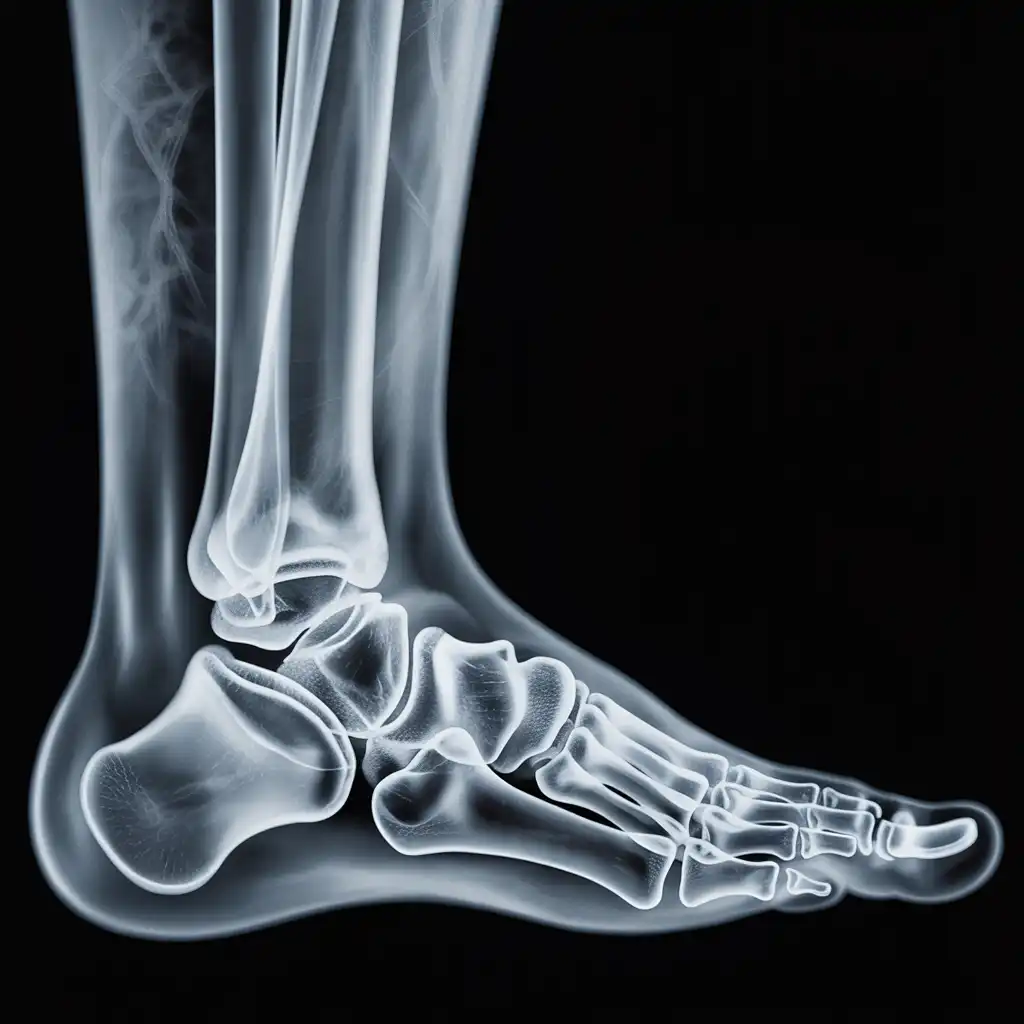

Una radiografia a domicilio è un esame radiologico eseguito da un tecnico specializzato che viene a casa tua con apparecchiature digitali portatili. L’esame si svolge sul posto, senza spostare il paziente e con la stessa qualità di una struttura ospedaliera.

Dopo l’acquisizione delle immagini, queste vengono inviate al medico radiologo che referta rapidamente e ti invia tutto in formato digitale. Un servizio comodo, sicuro e ideale per chi ha difficoltà negli spostamenti.